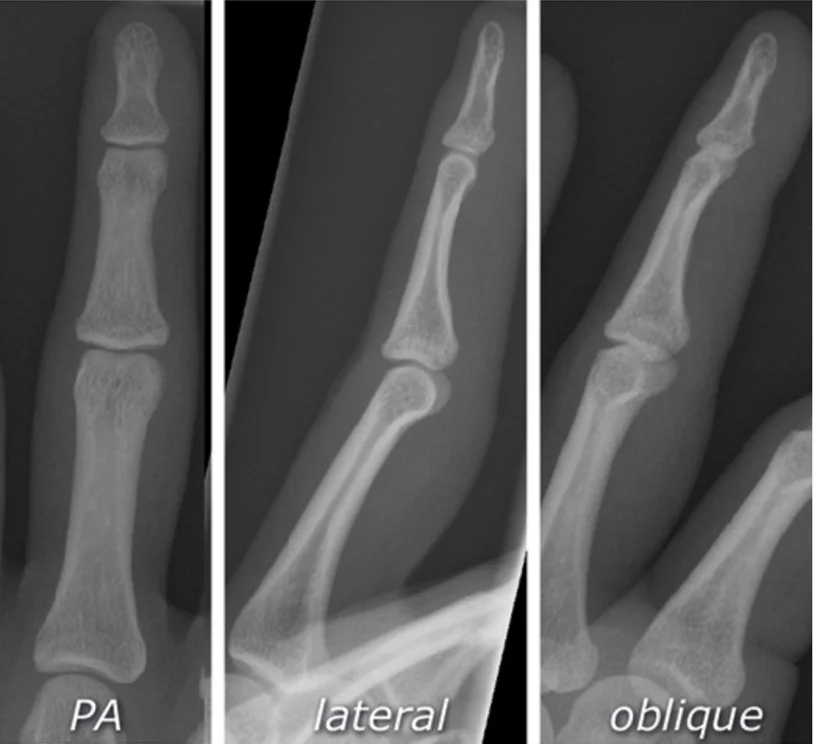

x-ray of hand

Reading Joints

- Name of joint

- Bone and Joint Alignment

- Position / Relations

- Joint space

- Articular surfaces